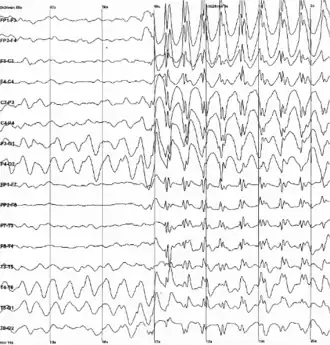

Données électrophysiologiques

L'enregistrement des données électroencéphalographiques est l'unique moyen de directement mettre en évidence l'activité épileptique. En effet, l'électroencéphalographie (EEG) permet d'enregistrer de manière directe l'activité électrique produite au niveau le plus élémentaire par les neurones. Contrairement aux autres techniques d'enregistrement, l'EEG fournit des informations en temps réel et avec une excellente résolution temporelle de l'ordre de la milliseconde (voir figure). Cet examen est incontournable pour le diagnostic et la classification des épilepsies.

Les premières expériences faites chez l'homme datent de 1924 et les premières publications sont parues en 1929 bien qu'elles aient débuté nettement plus tôt chez l'animal (dès 1875 par le physiologiste anglais Caton). Depuis, un nombre toujours plus grand de recherches lui a été consacré afin d'en savoir toujours plus sur la physiopathologie associée, la nature des rythmes observés, l'utilité clinique et ce dans de multiples domaines (problème du sommeil, épilepsie, démences, potentiels évoqués…). L'épilepsie représente un des plus gros thèmes associés à l'EEG.